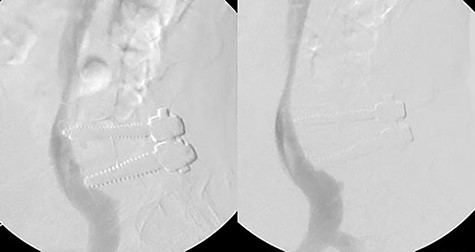

During the procedure, the patient was placed supine and a venous sheath was placed in the right femoral vein by vascular surgery. After turning the patient to prone position, the sheath was secured away from the hip bolster with tape to assure the line remained unkinked and functional (Fig. 2). A prone venogram was taken, which showed the right sided hardware indenting the IVC and right common iliac vein. A small posterior lumbar incision was made 3.5 cm to the right of midline over the hardware, which was exposed via a Wiltse approach. The right sided screws and rod were removed (Fig. 3). After removal, bleeding through the pedicle screw tracts was not observed. With the patient still in the prone position, a venogram was taken immediately after screw removal and showed no extravasation of contrast. It also showed that there was no longer indentation on the IVC and the right common iliac vein (Fig. 4). Thus, no further intervention was required. The incision was closed and the venous sheath removed. The postoperative course was uncomplicated.

Venous sheath placed through right femoral vein (left). Planned incision line with venous sheath held in place by tape (red arrow) (right).

Venogram showing right hardware indenting right common iliac vein and IVC (left). Postoperative venogram displays indentation no longer present after hardware removal (right).